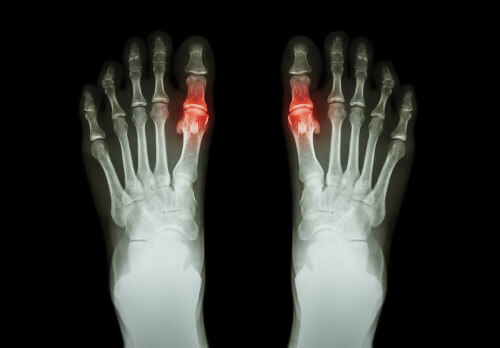

To samo dotyczy dny moczanowej, czyli podagry, która powstaje na skutek nadmiernej ilości kwasu moczowego, który osadza się w stawach. Z drugiej strony należy zauważyć, że stan zapalny stawów może nawet wiązać się z zawodem, który wykonujesz.

Każdy typ ma swoje cechy szczególne, a czas trwania objawów jest zwykle zmienny. Na przykład reumatoidalne zapalenie stawów jest symetrycznym zapaleniem stawów, które atakuje małe stawy, takie jak palce. Z drugiej strony dna moczanowa zwykle pojawia się jako zapalenie stawów w pojedynczym stawie.